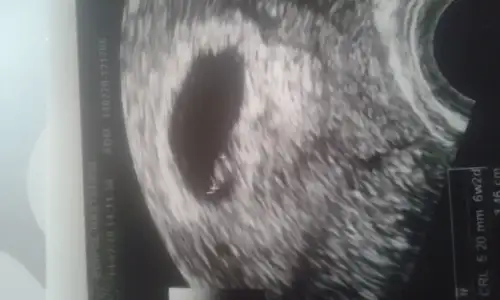

Önümüzdeki hafta hepimiz güzel haberlerle doldururuz burayı inşallah. Benim yarın sabah kalp sesini dinlemek için randevum var ama kalp sesinin yanında kanama alanı azalmıştır inşallah diyorum